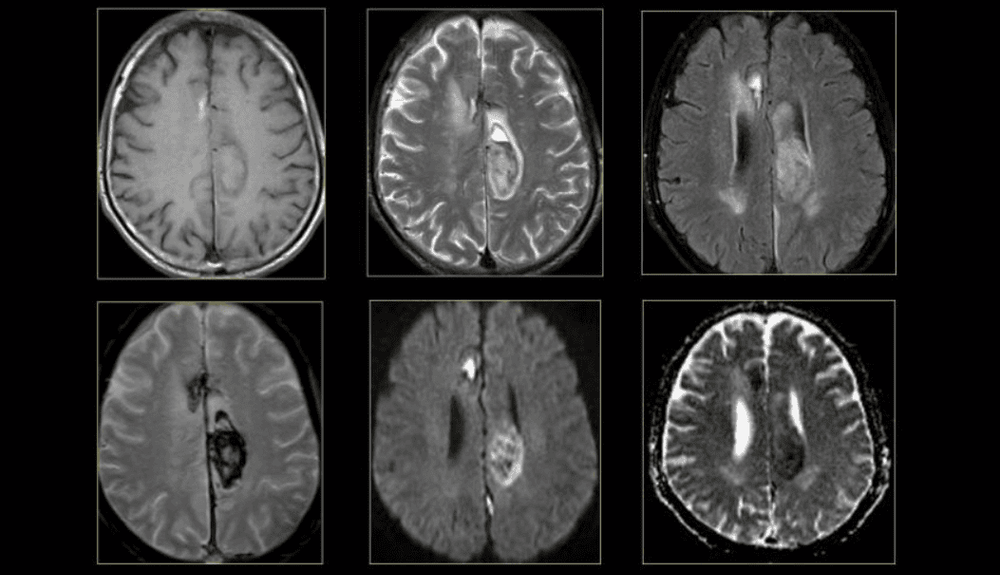

3.1 MRI của não và tủy sống

MRI là phương pháp xét nghiệm hình ảnh được sử dụng thường xuyên nhất đối với não và tủy sống. MRI thường được thực hiện để giúp chẩn đoán:

- Chứng phình động mạch não

- Rối loạn của mắt và tai trong

- Đa xơ cứng

- Rối loạn tủy sống

- Ảnh hưởng do chấn thương

- Khối u

- Chấn thương sọ não do va chạm

Một loại MRI đặc biệt - MRI chức năng của não (fMRI), có thể tạo ra hình ảnh của lưu lượng máu đến các khu vực nhất định của não. Nó có thể được sử dụng để kiểm tra giải phẫu não và xác định phần nào của não đang xử lý các chức năng quan trọng.

Điều này giúp xác định các khu vực kiểm soát chuyển động và ngôn ngữ quan trọng trong não của những người được xem xét phẫu thuật não. MRI chức năng cũng có thể được sử dụng để đánh giá thiệt hại do chấn thương đầu hoặc do các rối loạn như bệnh Alzheimer.